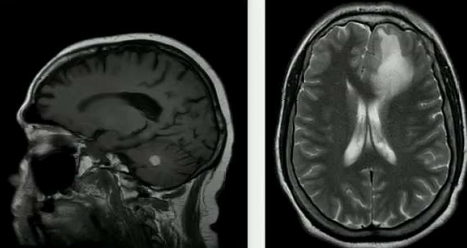

A 59 year old long-standing HIV patient presents with a CNS lesion. CD4 count is

Diffuse Large B Cell Immunoblastic Lymphomas are the most common cause of primary CNS lymphoma in patients with HIV. These are always EBV+ and have a poor prognosis. Tx with ARTs, radiation, high dose MTX w/leucovorin rescue, temozolomide and rituximab (Anti-CD20) followed by ARA-C with etoposide.